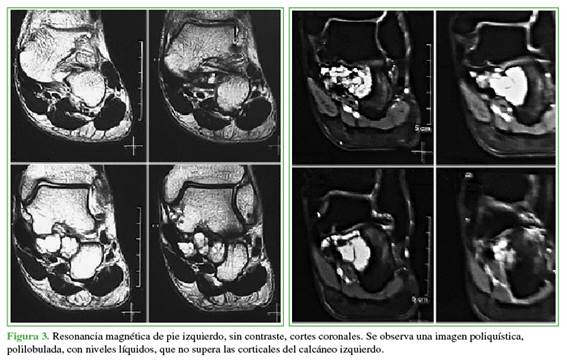

La radiografía de pie, de perfil, con carga muestra una imagen polilobulada, poliquística, que no supera las corticales del calcáneo izquierdo (Figura 2). En la RM sin contraste, se observa una lesión expansiva, excéntrica, de contornos bien definidos, polilobulada, con niveles líquido-líquido en su interior de 3,3 cm anteroposterior, 3,3 cm transversal y 2,7 cm cefalocaudal (Figura 3).